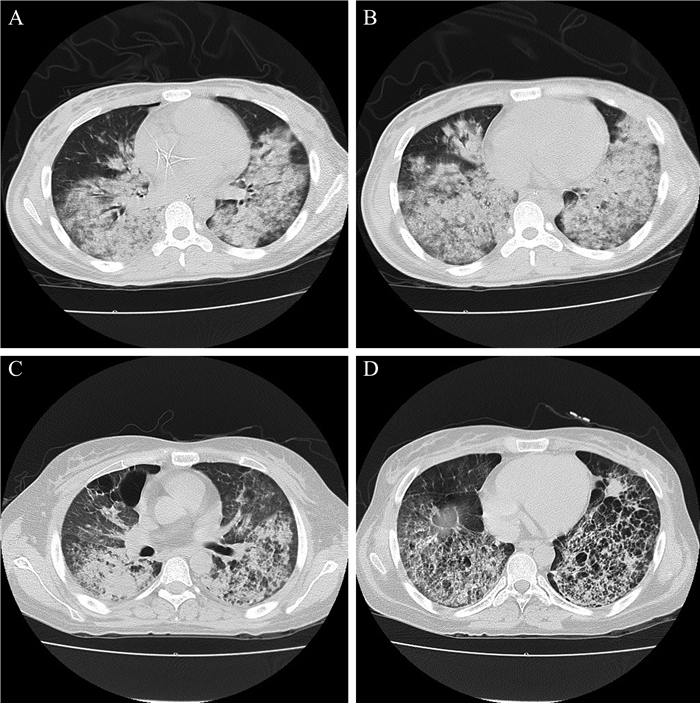

入住神经内科后4 d予抗感染、营养神经等治疗,患者有反复发热伴气促,每日最高体温均在39℃以上。完善胸部CT,结果提示双肺多发渗出,见图 1AB。动脉血气示氧分压51 mm Hg,考虑存在Ⅰ型呼吸衰竭转入内科ICU。转入内科ICU后,完善病原学检查并予哌拉西林钠他唑巴坦钠(4.5 g静脉滴注,每日3次,连用4 d)、莫西沙星(0.4 g/d静脉滴注,连用5 d)、替加环素(100 mg静脉滴注,每日2次,连用4 d)、伏立康唑(0.2 g静脉滴注,每日2次,连用6 d)等积极抗感染治疗。实验室呼吸道病原体9项(包括嗜肺军团菌1型-IgM、肺炎支原体-IgM、肺炎衣原体-IgM、Q热立克次体-IgM、腺病毒-IgM、呼吸道合胞病毒-IgM、甲型流感病毒IgM、乙型流感病毒-IgM、副流感病毒-IgM)、肺炎支原体血清学、多次纤维支气管镜(纤支镜)检查及肺泡灌洗病原学检查结果均无异常。风湿体液免疫全套、巨细胞病毒、EB病毒抗体以及多次真菌D -葡聚糖、GM试验均无异常。患者仍反复气促、存在呼吸衰竭,在征得家属同意后行经皮气管切开术呼吸机辅助通气。由于患者体温反复升高,病因不明,遂行纤支镜下肺活检。肺活检病理报告:可见肺泡间隔增宽,纤维母细胞增生,伴灶性坏死,部分区域肺泡塌陷,部分肺泡可见肺泡上皮脱落,腔内见纤维素样渗出与泡沫细胞、炎症细胞混合而成的栓子样物,偶见机化现象,形态考虑AIP伴肺泡损伤(图 2)。予甲泼尼龙80 mg每日2次治疗,1周后加用环磷酰胺0.4 g每周1次,共7次,累积量共2.8 g。25 d后经脱机训练后脱机成功并无再发热。肾上腺皮质激素(激素)逐渐减量并拔除气切套管,一般情况良好出院。患者出院后定期返院复查,胸部CT可见双肺斑片状、网格状阴影,范围较前缩小,见图 1CD

图 1 一例AIP患者的影像学检查结果 A、B:2017年4月5日转入ICU时患者的胸部CT,双肺可见多发边缘模糊的片状稍高密度影,以双肺下叶为主;C、D:2017年11月13日患者随访的胸部CT,双肺可见斑片状、网格状阴影,范围较前缩小